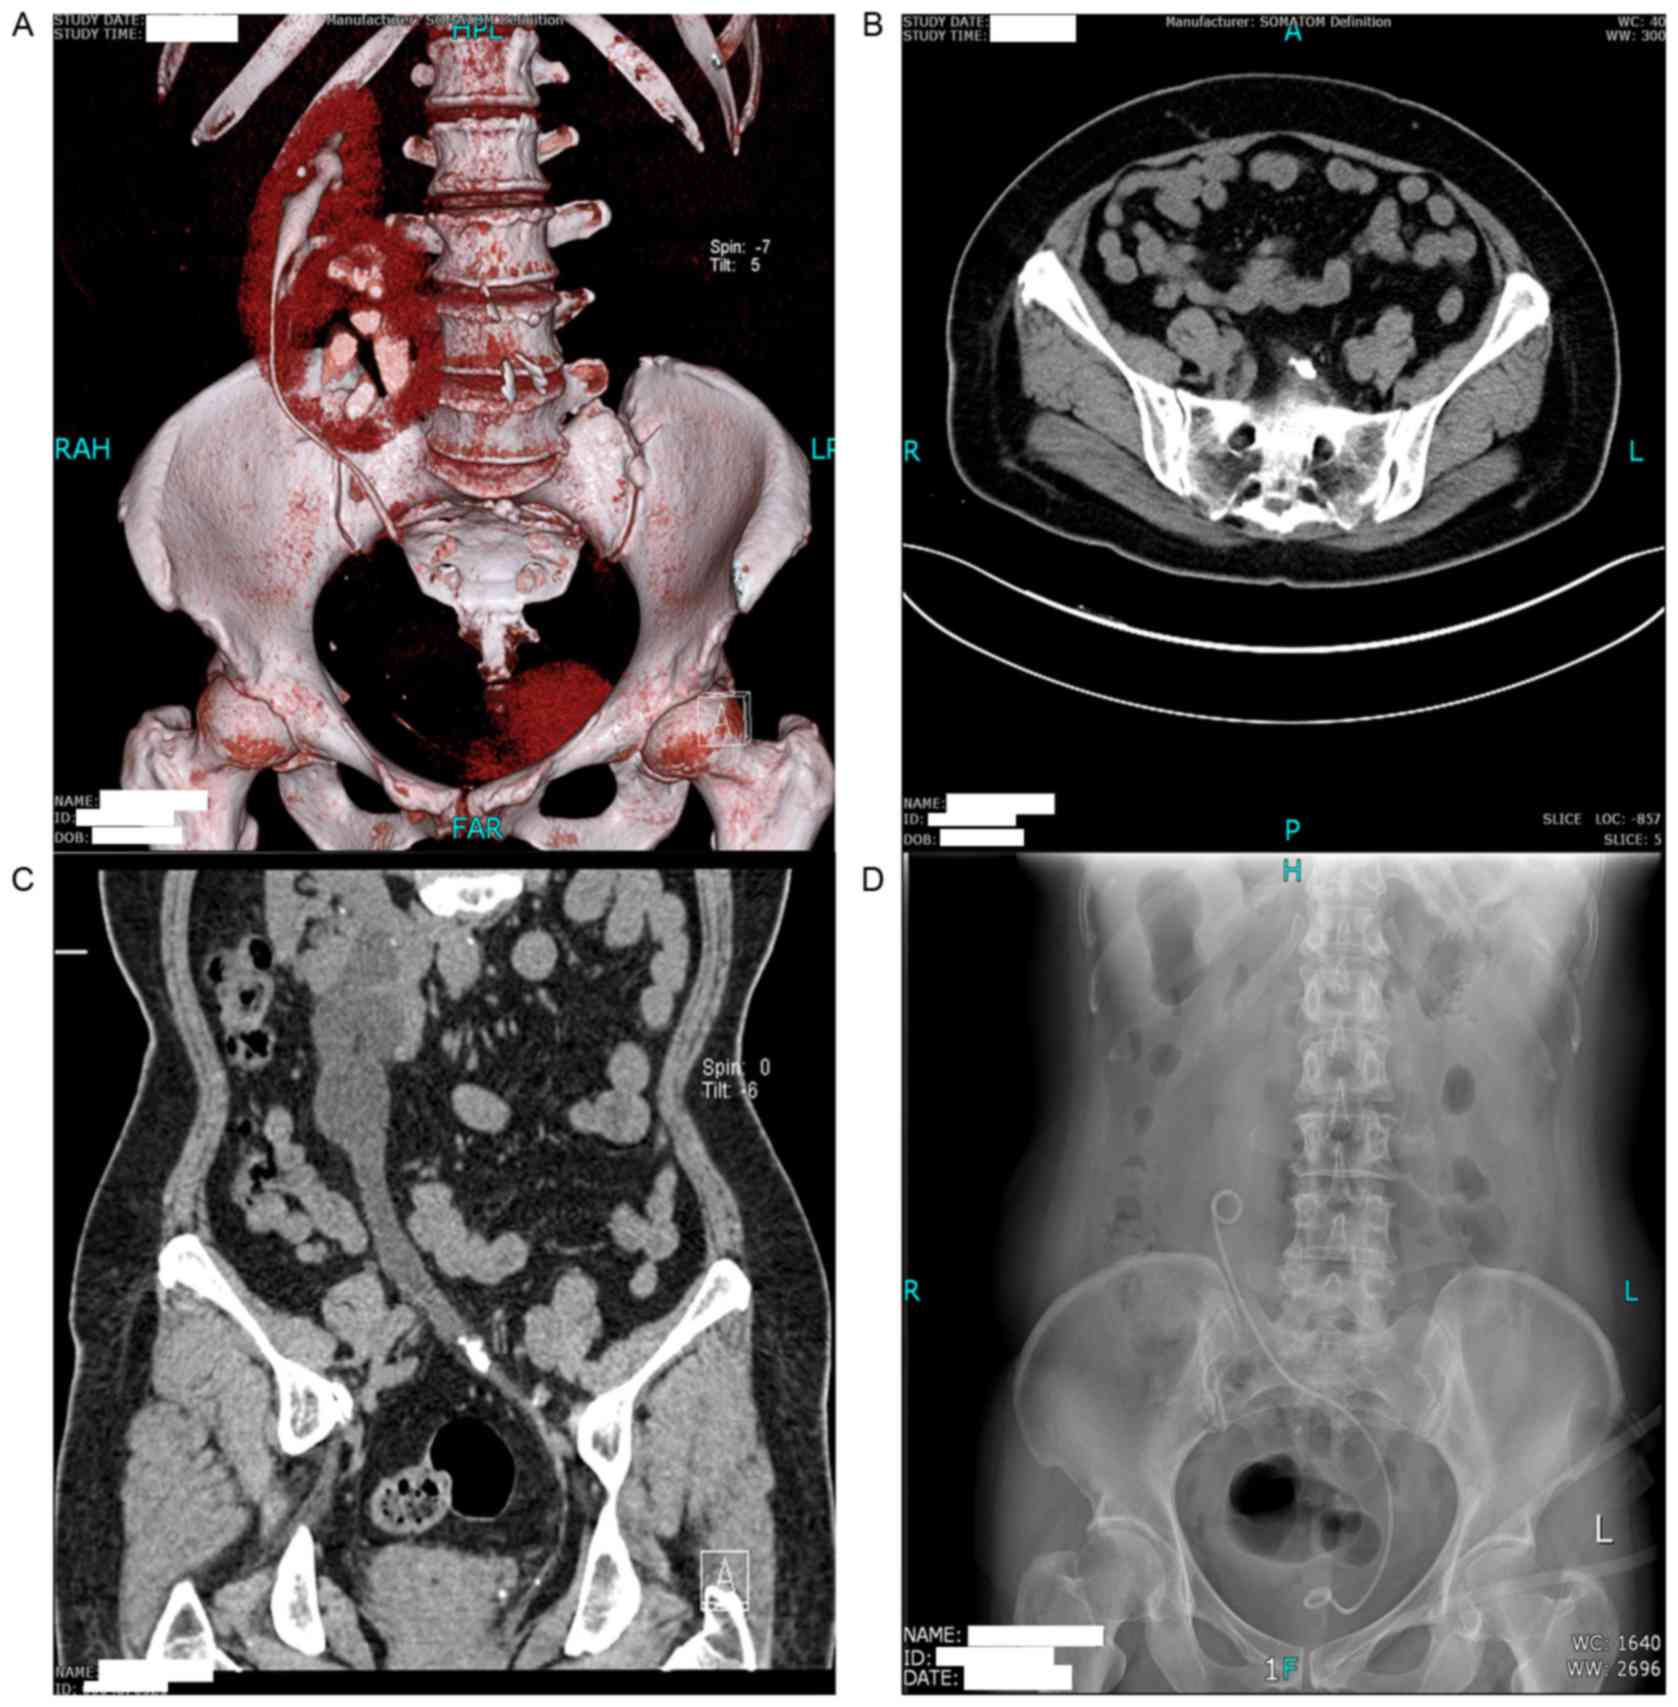

Management of upper urinary tract calculi in crossed fused renal …

X-ray images of the kidney, ureter, and bladder. (A) Pretreatment …

Plain X-ray KUB showing right renal pelvic calculus with the stainless …